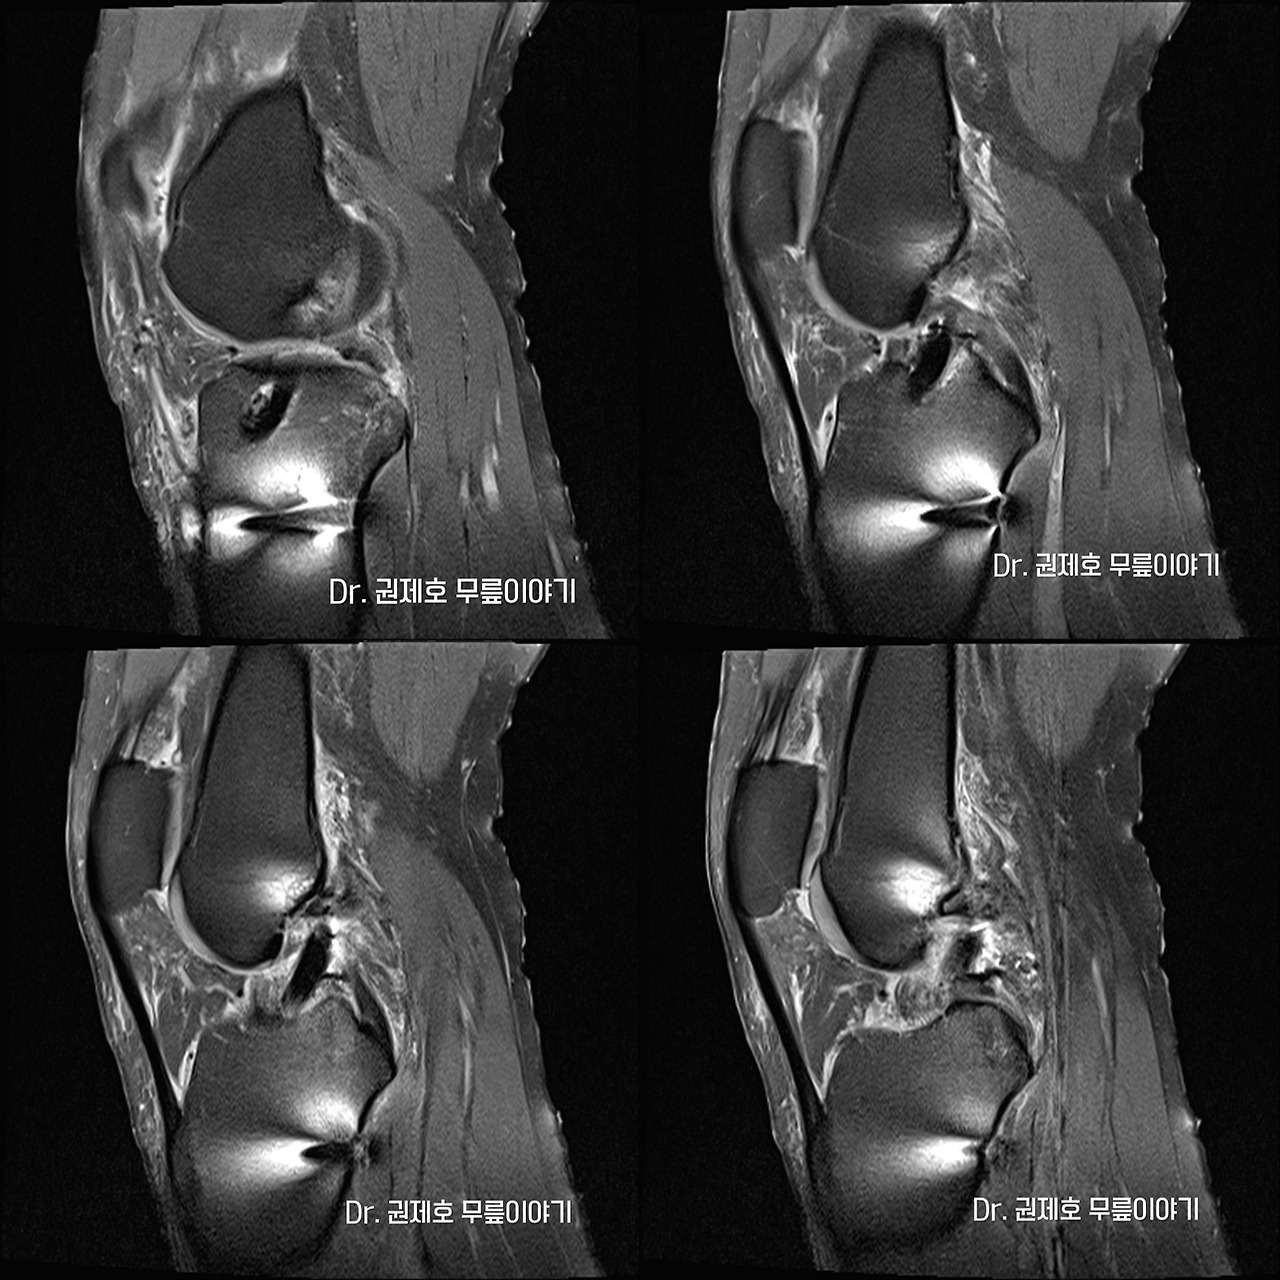

전방십자인대파열 타가건 재건술 (2).jpg 환자분의 MRI

의심되는 부위를 객관적으로 확인하는 방법은 현재는 MRI 밖에 없습니다. 십자인대 파열은 옆에서 보는 MRI 영상으로 진단하게 되며 위의 사진에서 보면, 화살표가 있는 부위가 전방 십자인대가 파열된 모습입니다.